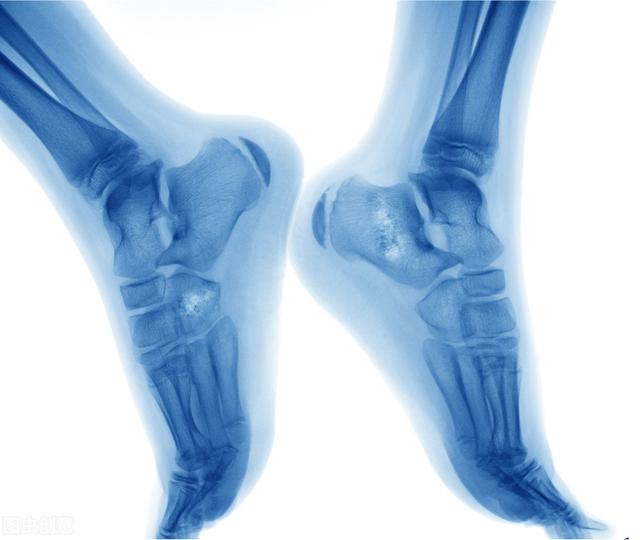

骨癌早期有三处痛感(年轻人容易被骨癌)

当在骨骼中检查出癌症时,要么是原发性骨癌,要么是继发性骨癌。骨癌有很多的症状,最常见的是疼痛,其他症状包括腰背疼痛,骨折,贫血,食欲不振和体重减轻等。如果有这些症状,一定要尽早去检查,从而得到及时的治疗。

原发性骨癌并不常见,而且儿童和年轻人患骨癌的风险要高于老年人。骨癌的发展可能涉及遗传和环境因素,骨痛是很常见的症状。如果正在经历持续的骨痛,一定要去看医生,很有可能是骨癌的症状。